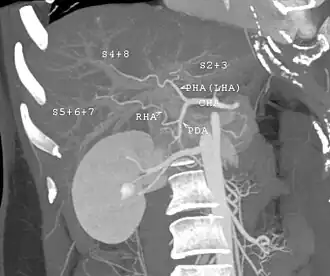

With the recent advances of noninvasive imaging, living liver donors usually have to undergo imaging examinations for liver anatomy to decide if the anatomy is feasible for donation. The evaluation is usually performed by multidetector row computed tomography (MDCT) and magnetic resonance imaging (MRI). MDCT is good in vascular anatomy and volumetry. MRI is used for biliary tree anatomy. Donors with very unusual vascular anatomy, which makes them unsuitable for donation, could be screened out to avoid unnecessary operations.

-

MDCT image. Arterial anatomy contraindicated for liver donation -

MDCT image. Portal venous anatomy contraindicated for liver donation -

MDCT image. 3D image created by MDCT can clearly visualize the liver, measure the liver volume, and plan the dissection plane to facilitate the liver transplantation procedure. -

Phase contrast CT image. Contrast is perfusing the right liver but not the left due to a left portal vein thrombus.